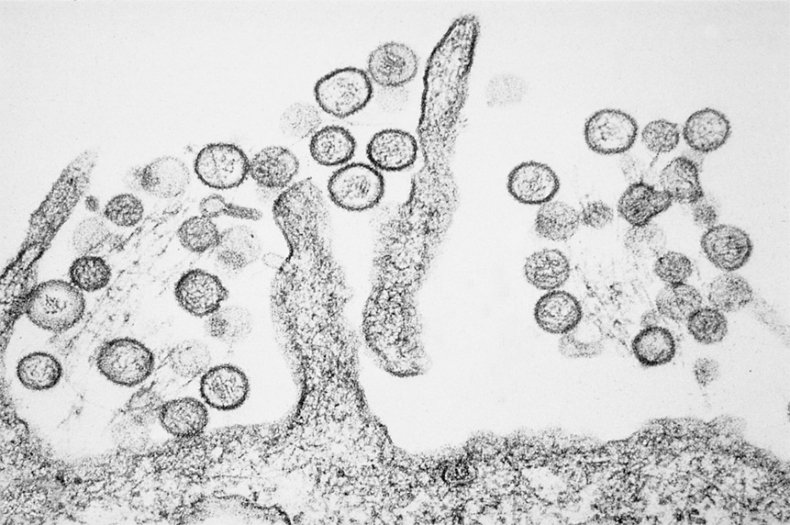

Рассмотрение историй болезни этих пациентов и анализ образцов крови и тканей при вскрытии вирусологами CDC показали, что причиной был один инфекционный агент. (Рисунок 12.1 на вклейке.) Этот агент был идентифицирован как хантавирус3, член семейства трансмиссивных вирусов Bunyaviridae4. Затем ученые, специалисты по молекулярным методам изучения генома вируса, сообщили, что выделенный хантавирус сильно отличается от известных штаммов, которые обычно вызывают геморрагические лихорадки и заболевания почек, но не острое повреждение легких. Обнаруженное заболевание было названо хантавирусным пульмональным синдромом1-3. Государственное наблюдение за хантавирусными инфекциями в Соединенных Штатах было тогда инициировано Центром инфекционных заболеваний. В 1995 году болезнь стали отслеживать и регистрировать на национальном уровне. К марту 1995 года в 20 штатах было выявлено около 106 пациентов с хантавирусным пульмональным синдромом, более половины из них погибли. Обычно симптомы включали лихорадку, мышечную боль, кашель, тошноту, рвоту и головную боль, которые продолжались от 4 до 15 дней и в итоге приводили к госпитализации пациентов. При поступлении в больницу у большинства пациентов отмечались лихорадка, низкое кровяное давление, малое количество тромбоцитов (клеток, необходимых для свертывания крови) и аномалии (если говорить точнее, инфильтраты) в легких, заметные на рентгеновских снимках. Какое-то время спустя у пациентов развивался отек легких: состояние, при котором легкие постепенно наполняются внесосудистой жидкостью. По сей день никто точно не знает, каким образом хантавирус провоцирует такие симптомы, хотя недавно обнаруженные свидетельства предполагают высвобождение определенных белков: возможно, цитокинов и хемокинов, которые во многом регулируют иммунный ответ организма. Во время воспаления, вызванного инфекцией, важную роль в патогенезе заболевания играет так называемый цитокиновый шторм. Никаких других методов лечения, кроме поддерживающей терапии и профилактики, для облегчения симптомов хантавирусной инфекции не существует. После того как информация о вирусе стала достоянием общественности, на юго-западе США сократился поток туристов, пришли в упадок соответствующие отрасли бизнеса. Поэтому первоначальное название вируса, «вирус четырех углов», отсылающее к региону, где болезнь возникла, было изменено. Вследствие политической и экономической необходимости сейчас вирус зовется Sin Nombre virus – «вирус без названия»1,5. Так «вирус четырех углов» обрел новую политическую корректность.

Иллюстрация к книге — Вирусы и эпидемии в истории мира. Прошлое, настоящее и будущее [i_028.jpg]

РИСУНОК 12.1. Электронная микрофотография хантавируса